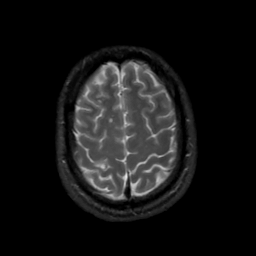

MR Study #3, February 24, 1991 -- Slice #41

[Home][Help][Clinical][Tour 1][Tour 2] Slice 41